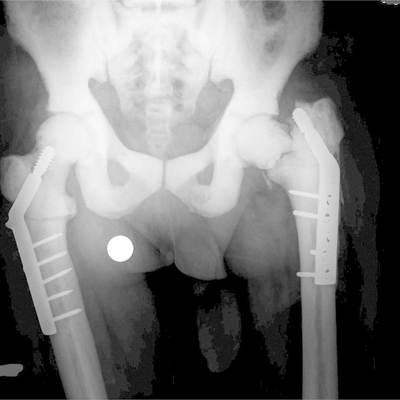

Click on an image below to view more info.